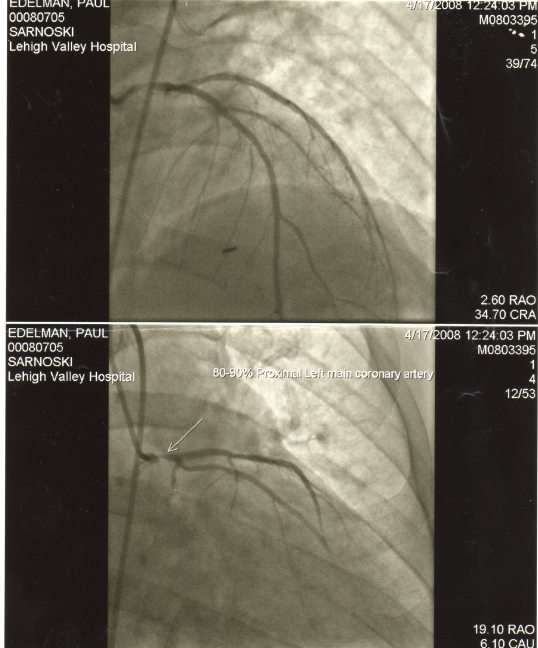

The cardiologist came into the room. He had informed me that I had a blockage, somewhere. He said he normally never offered a diagnosis of 100%, but he was 100% certain that I had one. He wanted me to check into the catheterization lab next door to his office. There, they would go up through my leg, and try to place a stent wherever the blockage was.

I was coming to, when I saw the cardiologist, my wife, and a friend at the foot of my bed. All I could make out was that it was worse than they thought. I did not grasp the technical way the doctor explained it. But my friend who was there, was an EMT, and she knew what it meant, and in shock blurted out, “a widow maker.” Again, I was still under the influence of the anesthesia, but as the fog wore off, the severity began to settle in.

I was now set up for an emergency triple bypass the next day. Not any time to go through those stages. First thing in the morning.